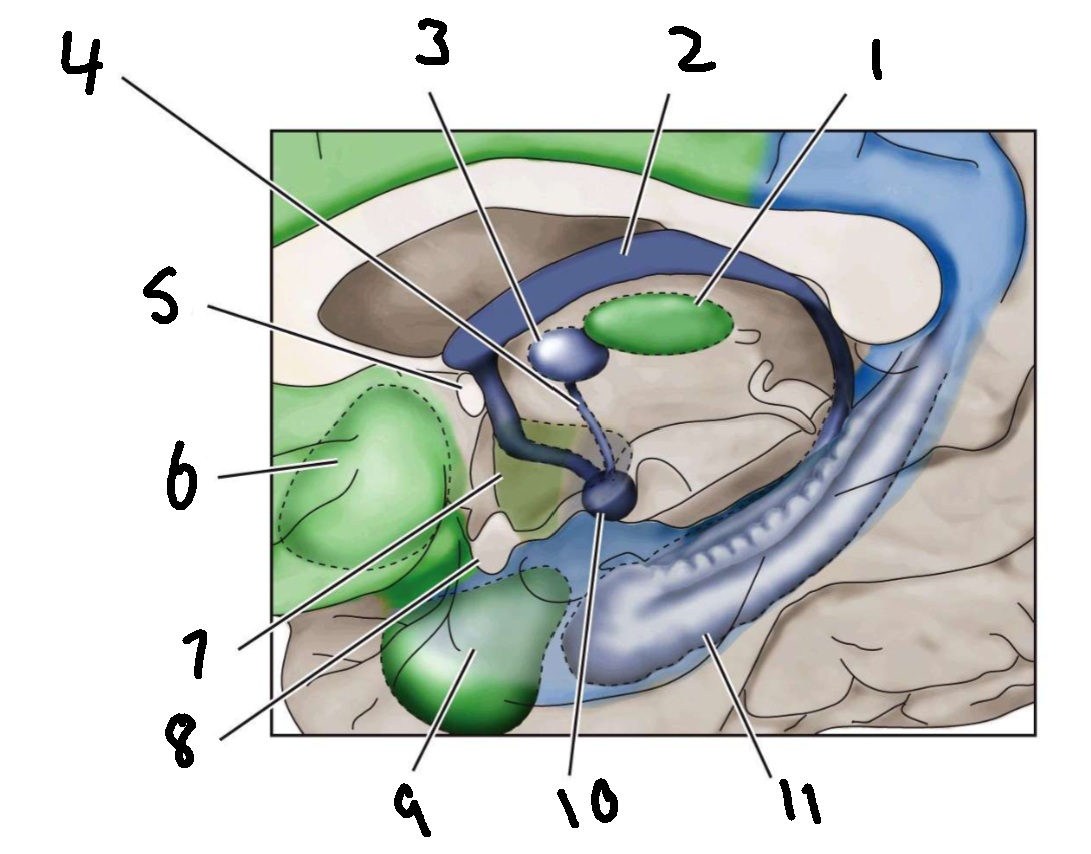

What is 1?

mediodorsal nucleus of the thalamus

What is 2?

fornix

What is 3?

anterior nucleus of the thalamus

What is 4?

mammillothalamic tract

What is 5?

anterior commissure

What is 6?

ventral basal ganglia

What is 7?

hypothalamus

What is 8?

optic chiasm

What is 9?

amygdala

What is 10?

mammillary body

What is 11?

hippocampus